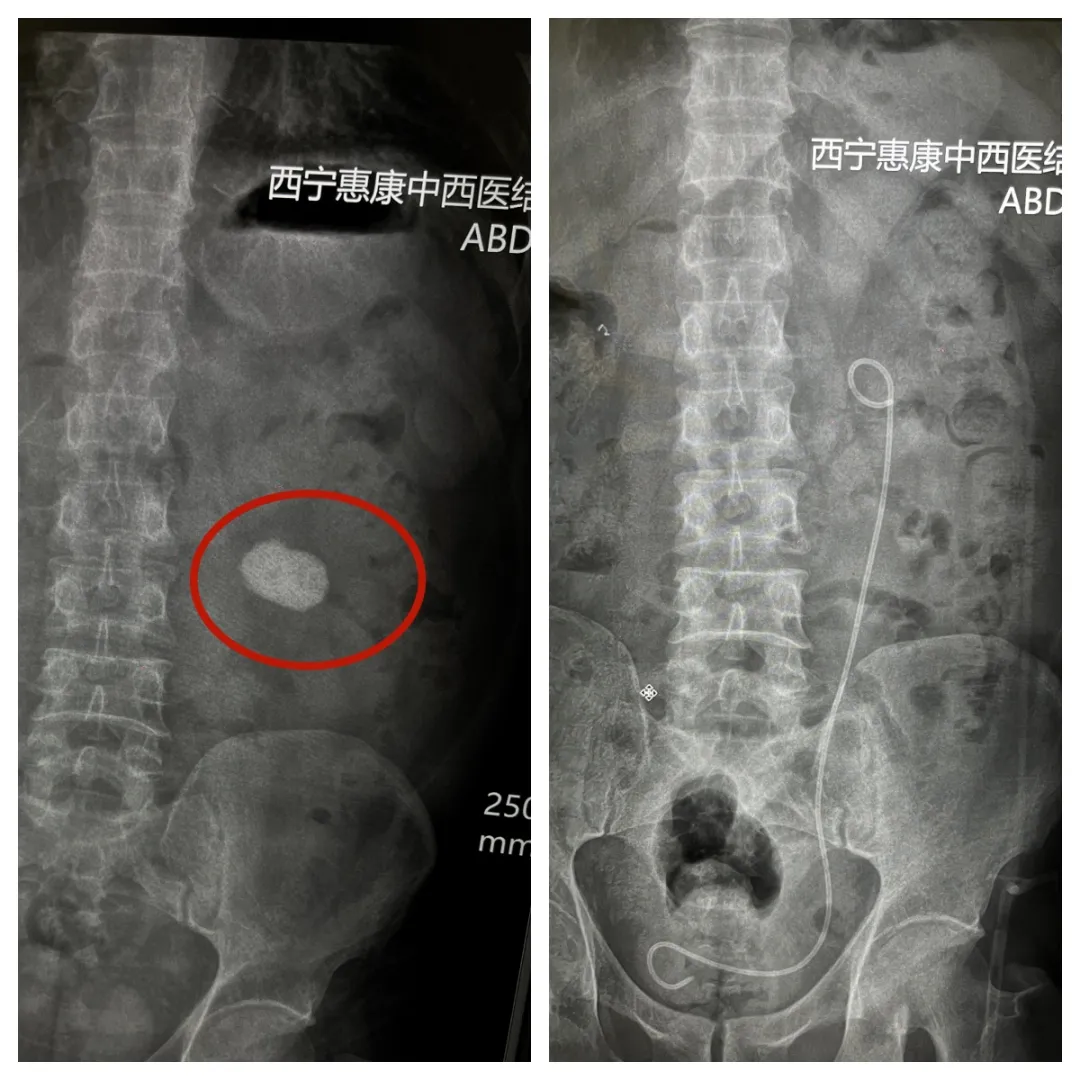

近日,我院泌尿外科团队应用微创碎石取石术,为一名巨型肾结石患者实施了微创手术治疗。该患者因左侧腰部间断性疼痛2年余入院,经术前评估与方案制定,完成了手术,术后患者恢复良好。

入院后,科室诊疗团队完善了相关检查。泌尿系三维CT重建显示:左肾中见鸡蛋大小的结石,结合患者病史及影像学特征,团队评估认为该结石具有手术指征。

为保障手术安全,泌尿外科组织麻醉科、影像科进行了多学科会诊。针对患者结石大、密度高、肾盏角度偏小的特点及手术时长不宜过长的考量,团队制定了详细的诊疗方案:经皮肾镜下钬激光碎石取石术,并设定了相应的激光能量参数,同时完成了术前风险告知。

近日,手术在全麻下实施。术中采用“蚕食法”将钬激光光纤贴近结石表面,将结石击碎,联合负压吸引装置清除碎石,最后置入双J管引流。过程顺利。

术后给予预防感染、补液利尿等治疗,护理团队仔细护理。术后复查提示结石已清除,双J管位置良好,患者生命体征平稳,顺利办理出院。